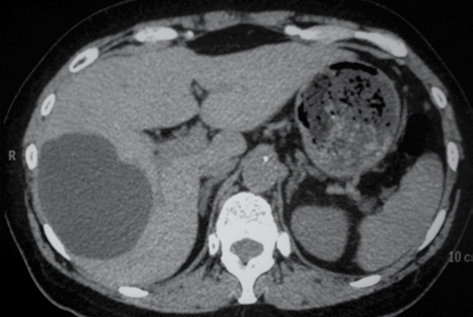

Observe a imagem a seguir.

O corte tomográfico computadorizado abdominal sugere